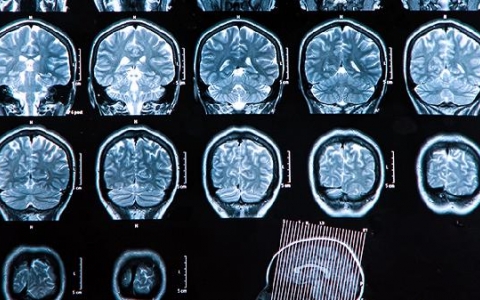

前几天,我接诊了一位45岁的患者,他因车祸导致头部受伤,出现头痛、恶心、呕吐等症状。我立即为他进行了详细的检查和问诊。通过头部CT扫描,我发现他脑内有淤血和肿胀